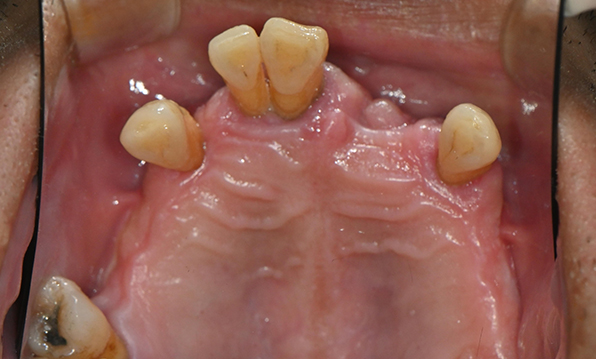

전체 임플란트가 필요한 경우

치아가 얼마 남아있지 않은 경우

치주질환이 심해, 치아가 있더라도 제 기능을 하지 못하는 경우

틀니 사용이 불편한 경우

잇몸뼈가 얇은 상태

전체 임플란트를 해야하는 환자들은

대부분 고령의 환자들로 오랜 틀니 사용

또는 노화로 인해 치조골이

거의 남아있지 않는 경우가 많습니다.

이 때, 치조골 이식을 병행하여 잇몸뼈 재건 후 안정적인 임플란트 식립을 하고 있습니다.

치료기간 : 2021.04.12~2021.09.15